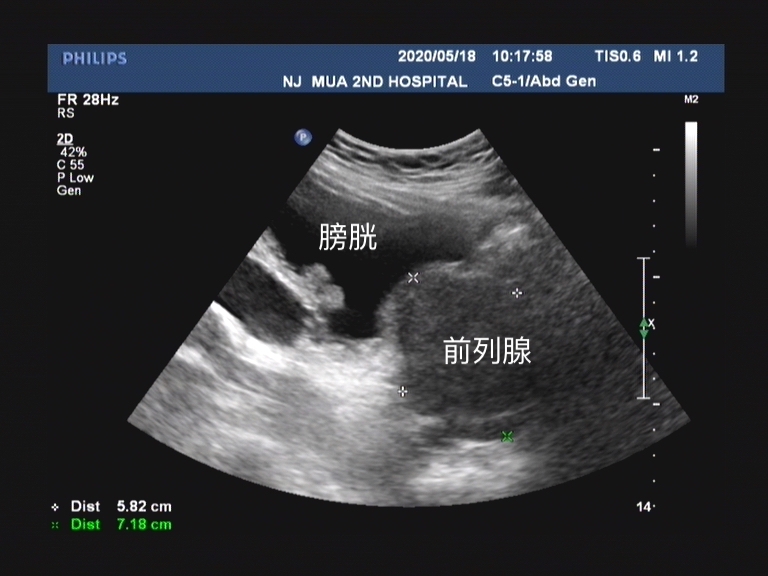

老王是一位诊断为前列腺增生的患者,他的 临床症状是非常典型的前列腺增生症状,涵盖了储尿期、排尿期和排尿后症状。

自己觉得 最困扰的症状就是尿频,夜尿一般是每晚3~5次 ,由于严重影响他的睡眠,所以这也是老王选择来口服药物治疗的最主要原因。 排尿等待的现象有 ,但是并不明显,当老王能排出小便后,还没有非常明显的排尿困难情况。 排尿以后有尿不尽感 ,但是完善检查以后并没有非常多的残余尿量。

老王的 国际前列腺症状评分IPSS评分是15分 (感兴趣的可以看下之前文章)。当然客观的检查数据 打破了老王的“自觉排尿顺畅”的信念 ,尿流率提示老王一次 排尿量是221.5ml;最大尿流率10.7ml/s;平均尿流率5.8ml/s;残余尿量20ml。 而我们正常男性的 最大尿流率的及格线是15ml/s,低于10ml/s时患者出现尿潴留或者其他排尿问题的情况就会较为明显。